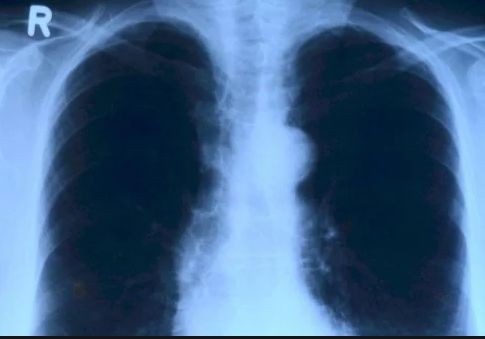

“武汉肺炎”病例激增,从中国入境新加坡必测体温!

新增病例中的这名52岁新加坡男子曾经到访武汉,但并未到过被认为是疫情源头的华南海鲜批发市场。如今,他已被隔离治疗,情况稳定。

若发现有任何类似于肺炎的可疑病例,将被直接送往医院进行隔离,再做进一步检查。